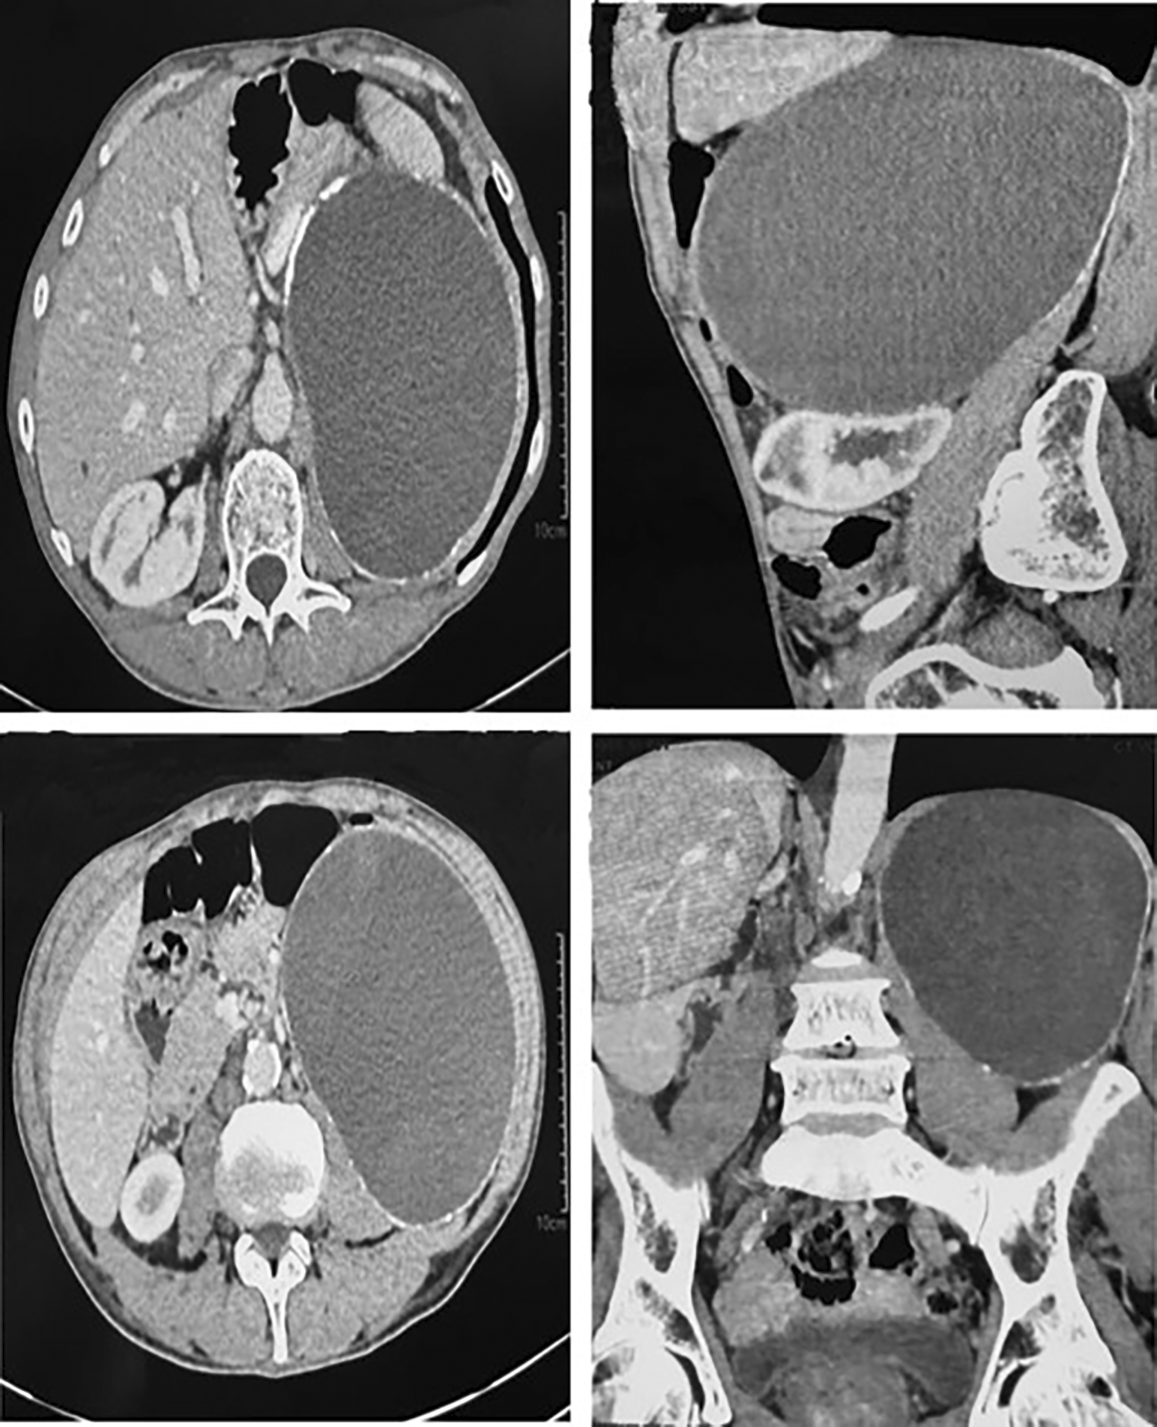

Contrast-enhanced abdominal CT ( Figure 1) showed a large, well-circumscribed, left retroperitoneal cystic mass (15 cm) displacing the spleen superiorly and kidney inferiorly. The left adrenal gland appeared displaced but morphologically normal. Mild left pyelocaliceal dilatation suggested ureteropelvic junction compression. No solid or enhancing components were seen. Possible diagnoses included liquefied adrenal hematoma or cystic lymphangioma.

Mild left pyelocaliceal dilatation is visible, suggesting ureteropelvic junction compression.